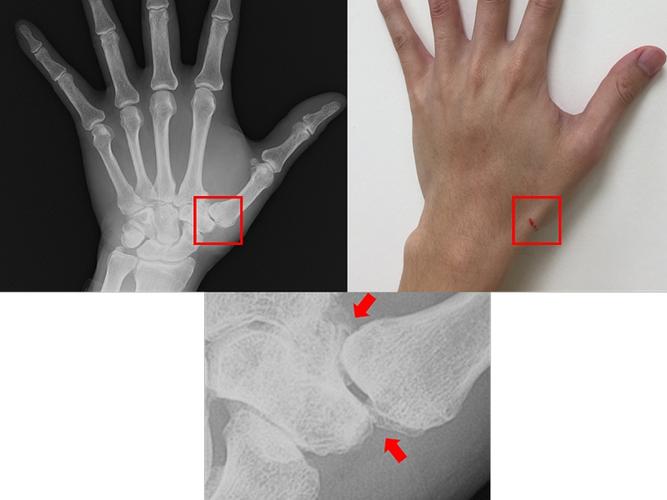

手腕骨刺图片,手腕骨刺

经x光摄影发觉拇指腕掌关节退化并骨刺增生的情形(图片/台大竹东分院